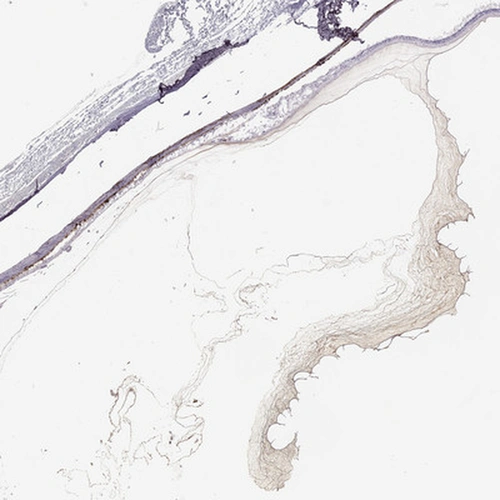

Immunohistochemical staining of human eye shows strong staining in positivity in vitreous humor.